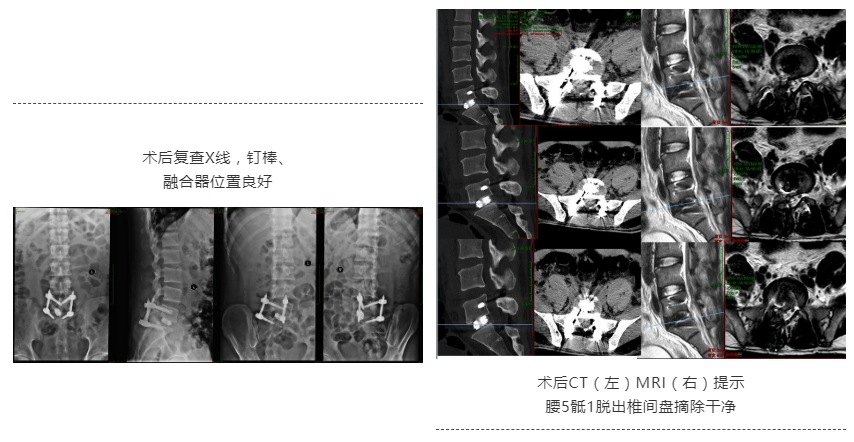

确定了手术方案、详细评估了手术相关并发症、并进行了详细的术前规划后,姜先生顺利接受了这场“只用5个小孔”解决问题的手术。

术后,姜先生恢复良好,腰痛、右下肢疼痛的情况明显好转。姜先生不禁竖起了大拇指为何升华教授的专业技术点赞。